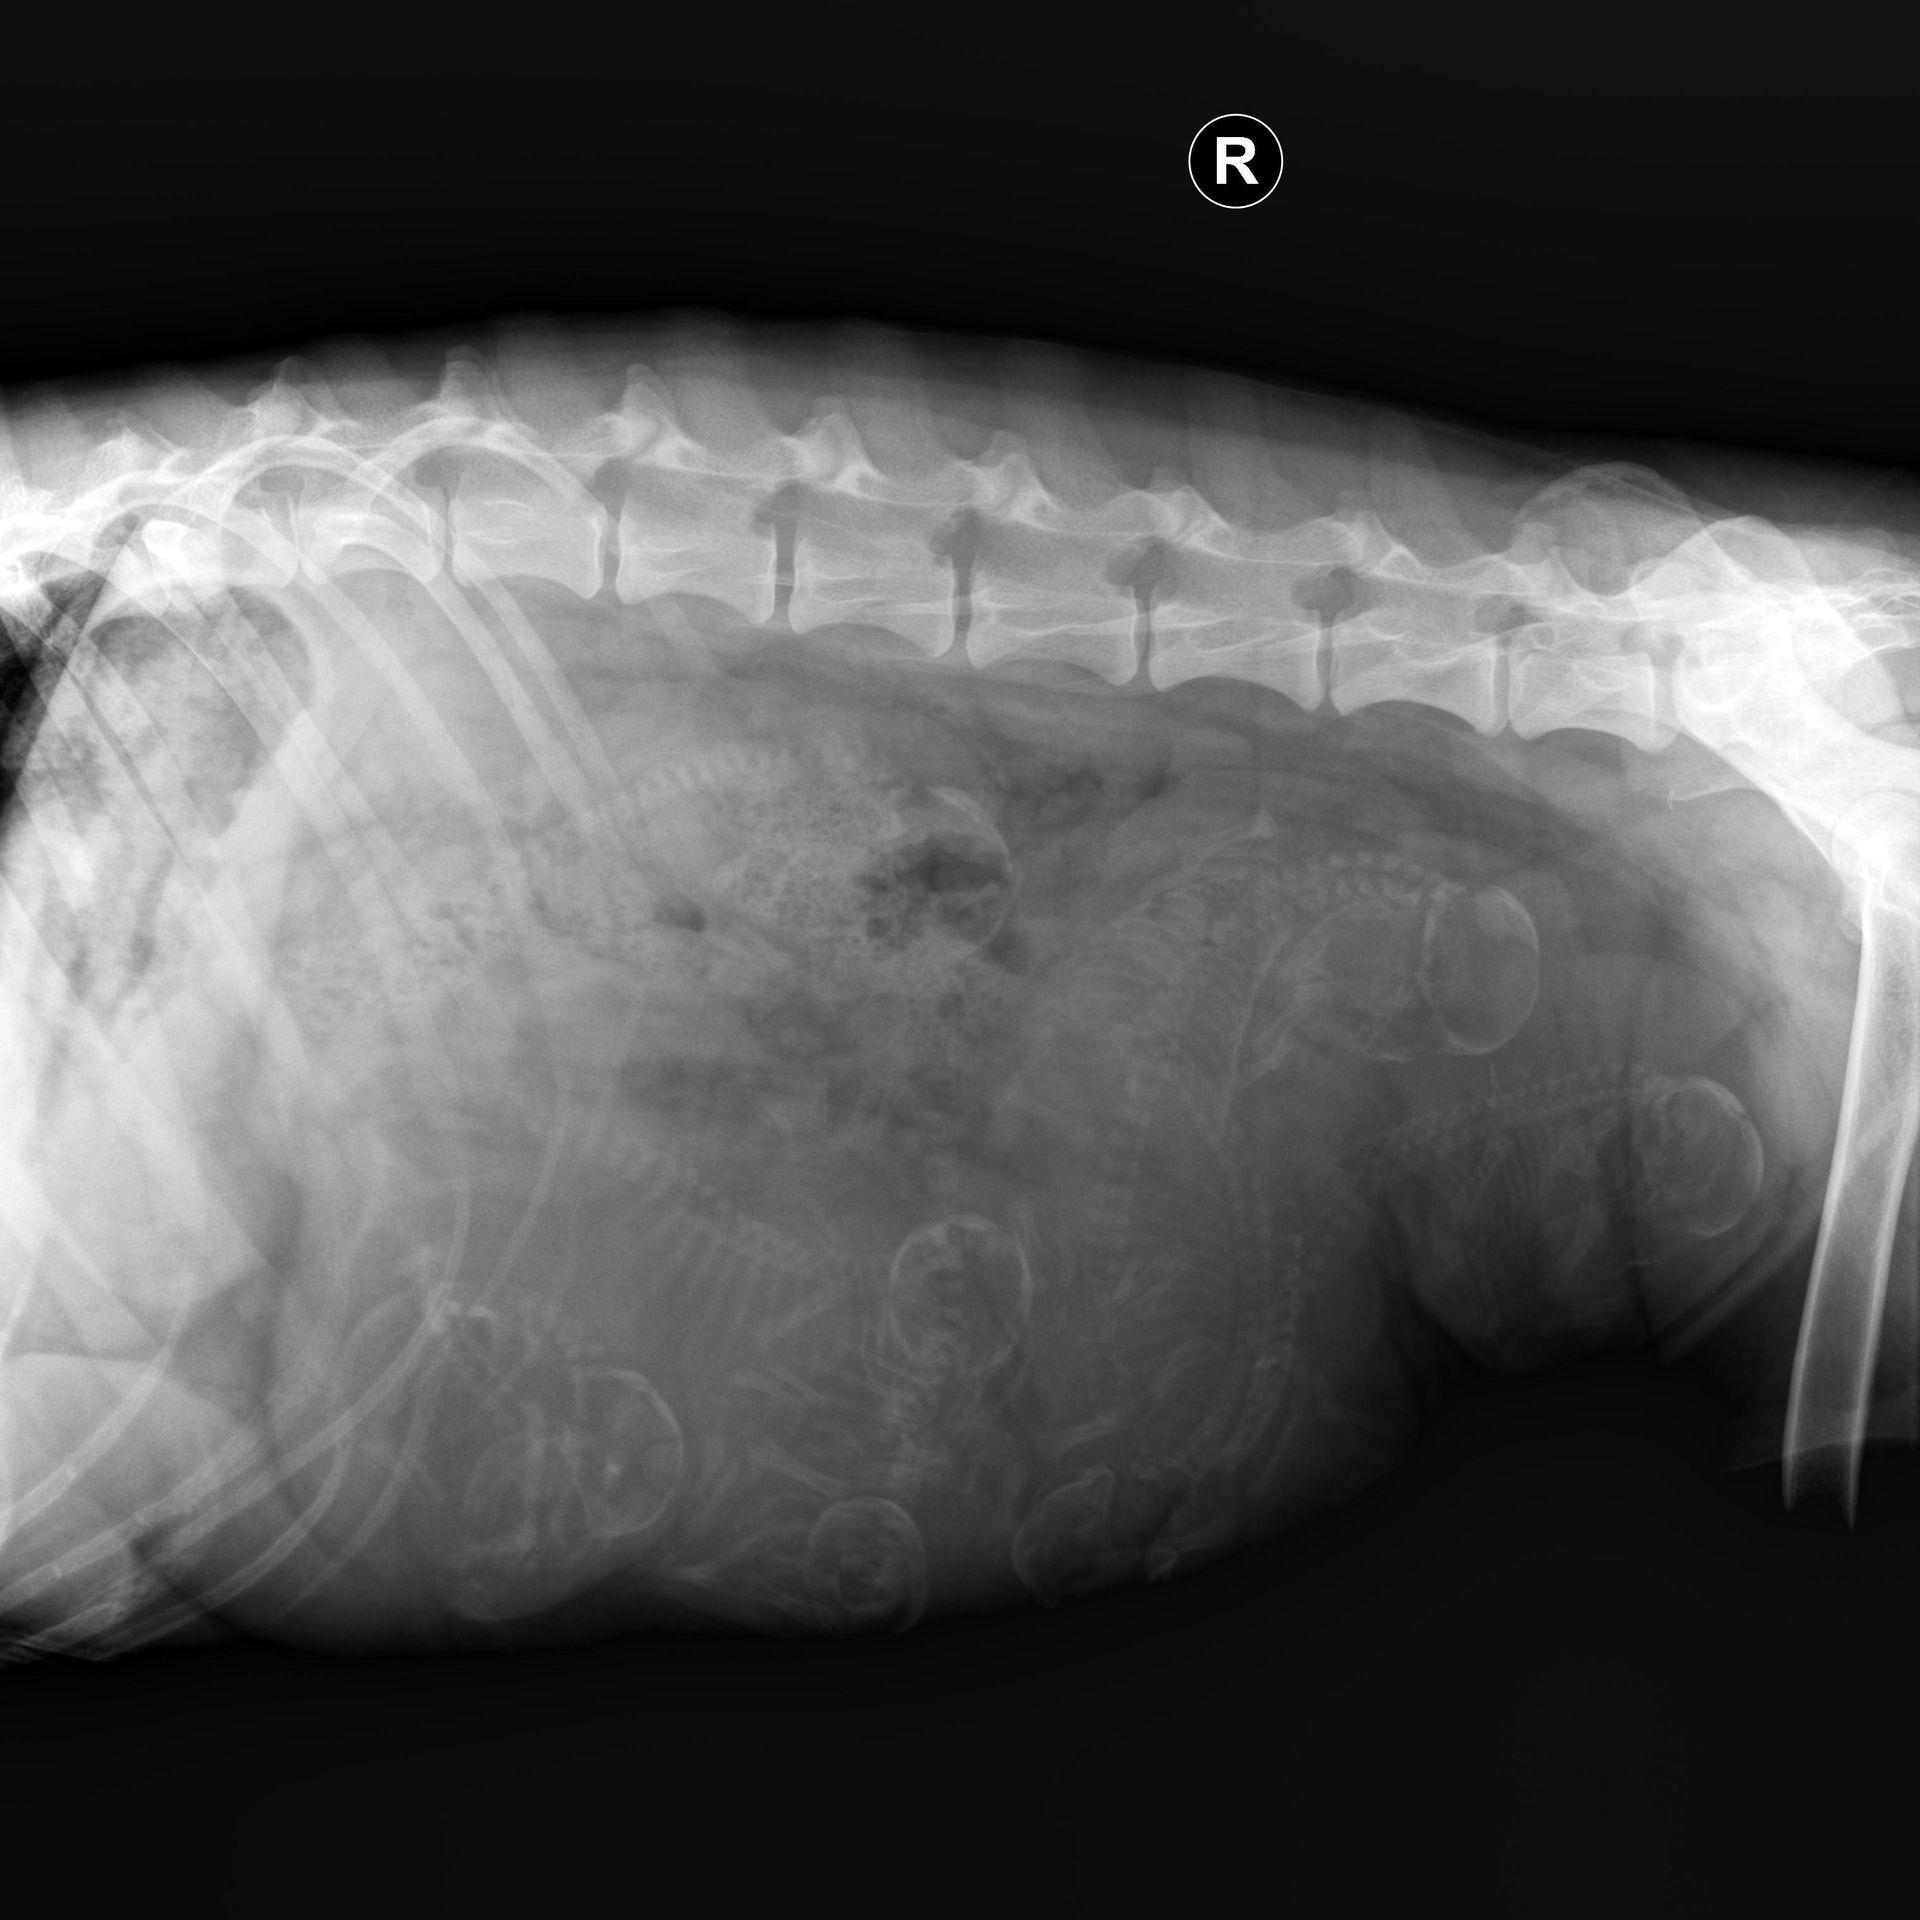

Am 04.03.2023 waren wir zum Röntgen um ziemlich sicher sagen zu können mit wie vielen Welpen wir rechnen dürfen. Meine Tierärzte und ich sind uns noch etwas uneinig ob es 7 oder 8 Babys sind, aber fest steht das wir definitiv 7 Babys erwarten! Ob dann noch ein achtes kommt werden wir sehen :D.